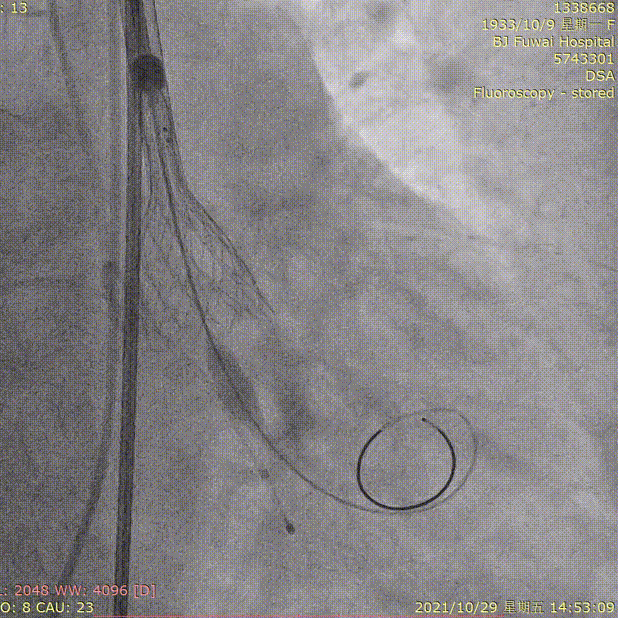

3.选择20mm球囊预扩

球囊预扩